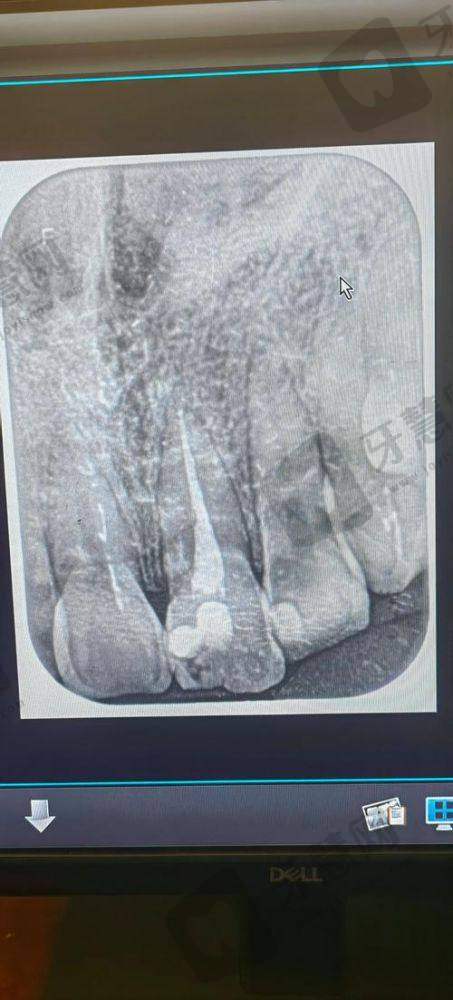

丰富的诊疗经验:艾军 医生作为北京西诺口腔(常营店)的主治医师,拥有长达36年的牙科诊疗经验。他曾在三等甲国有医院口腔科任职30余年,积累了丰富的口腔治疗技能。专精领域专长:艾军 医生在多个专精领域表现出色,尤其擅长种植牙、根管治疗以及儿童全口涂氟等项目。他技术娴熟、操作规范,能够有效实施微痛治疗,让患者在舒适的状态下完成治疗。凭借不错的医术和良好的医德,艾军 医生深受患者的信任和赞誉,在种植领域以及口腔美容修复领域有着丰富的临床经验。

种植牙手术费用:艾军 医生开展的种植牙手术费用一般在5000 - 30000元不等,这取决于种植体的品牌、种植的难度等。如果选择较为有名的进口种植体,费用会相对较高;而一些国产种植体价格则较为亲民。根管治疗费用:根管治疗的费用通常在500 - 2000元左右,根据牙齿的部位和根管的复杂程度有所波动。儿童全口涂氟费用:儿童全口涂氟的费用相对较低,大概在100 - 300元。北京西诺口腔(常营店)会根据患者的具体情况制定个性化的治疗方案,并明确告知费用详情。